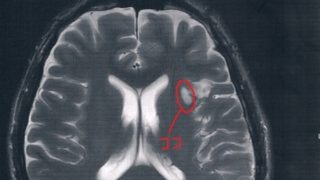

GLIOMA:手術後44ヶ月目の検査

半年前(2018/3/8)の検査の記録。ブログに追加するのを忘れていたらしい。2014/6/23の覚醒手術から約44か月になる。MRI検査の結果、半年前と比べても変化は無し!今回2018/3/8(手術後44か月)のMRI画像前回2017/9...